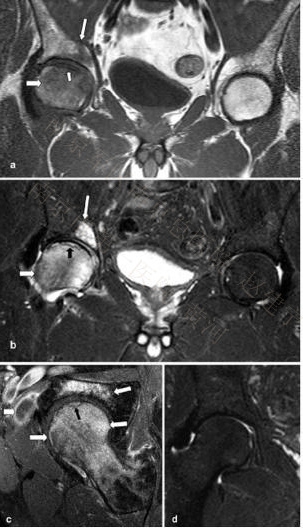

ONFH与TBME在MR表现上的区别:ONFH多为双侧发病(72%);软骨下病损低信号区(至少4mm厚,12.5mm长);T2-W像有典型的双线征(80%),T1-W像则表现为软骨下低信号带,ONFH常以典型的低信号带为最初表现,多数并无弥漫性的骨髓水肿。TBME多无软骨下病损区,即便有范围也较小,通常厚不足4mm,长不足12.5mm;多数患者有明显的关节积液;髋臼可有累及(17%);多为单侧;长期的关节液渗出导致周围软组织改变。

58岁男性。(a, b) T1-W及T1快速翻转恢复图像(STIR)均可见右侧股骨头内弥漫性的骨髓水肿(粗箭头),同时软骨下可见线性的低信号(小箭头),甚至髋臼区亦可见骨髓水肿信号(细长箭头)。(c) 脂肪增强抑制T1-W自旋回波图像(SE)显示股骨头及髋臼弥漫性骨髓水肿信号(箭头),软骨下线性改变(黑箭头)以及髂腰肌滑囊炎性改变信号(粗箭头)。(d) 11个月后T1 STIR图像见骨髓水肿区已完全消失。

45岁,长期服用皮质类固醇激素,左髋疼痛2月。T1-W(a)及脂肪抑制T2-W像(b)均可见左髋股骨头内有典型的条带状信号(粗黑箭头)以及弥漫性的骨髓水肿(粗白箭头);在无症状的右髋中也可见到这一典型的条带状信号(均为细箭头),但并无骨髓水肿改变,表明ONFH尚处于病变的早期阶段。